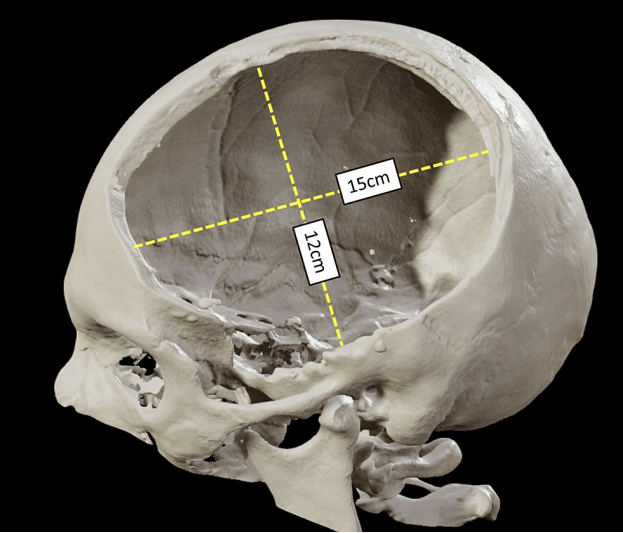

Describe a craniostomy

Holes are drilled into the skull to drain haematoma and reduce intracranial pressure

Describe decompressive craniectomy

Reduce intracranial pressure after malignant MCA stroke

Bone flap is removed until swelling is reduced